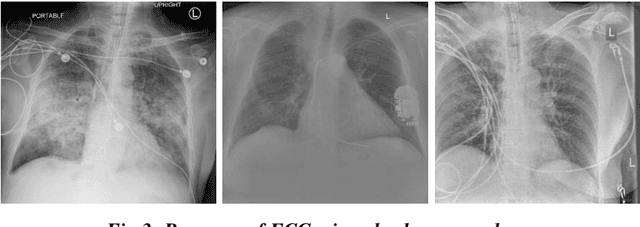

Abstract:Background and Objective: Artificial intelligence (AI) methods coupled with biomedical analysis has a critical role during pandemics as it helps to release the overwhelming pressure from healthcare systems and physicians. As the ongoing COVID-19 crisis worsens in countries having dense populations and inadequate testing kits like Brazil and India, radiological imaging can act as an important diagnostic tool to accurately classify covid-19 patients and prescribe the necessary treatment in due time. With this motivation, we present our study based on deep learning architecture for detecting covid-19 infected lungs using chest X-rays. Dataset: We collected a total of 2470 images for three different class labels, namely, healthy lungs, ordinary pneumonia, and covid-19 infected pneumonia, out of which 470 X-ray images belong to the covid-19 category. Methods: We first pre-process all the images using histogram equalization techniques and segment them using U-net architecture. VGG-16 network is then used for feature extraction from the pre-processed images which is further sampled by SMOTE oversampling technique to achieve a balanced dataset. Finally, the class-balanced features are classified using a support vector machine (SVM) classifier with 10-fold cross-validation and the accuracy is evaluated. Result and Conclusion: Our novel approach combining well-known pre-processing techniques, feature extraction methods, and dataset balancing method, lead us to an outstanding rate of recognition of 98% for COVID-19 images over a dataset of 2470 X-ray images. Our model is therefore fit to be utilized in healthcare facilities for screening purposes.